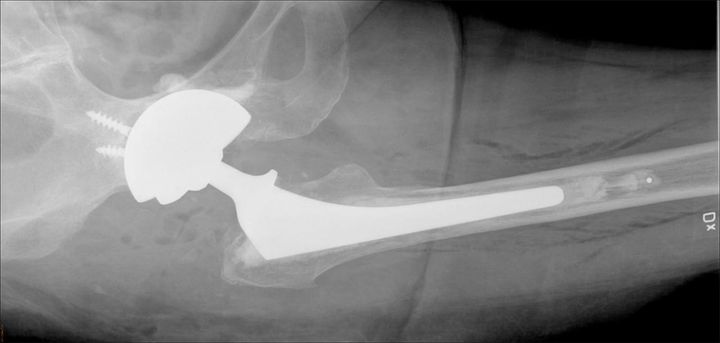

Dubbelskålar kan minska risk för att höftprotesen hoppar ur led

– Vid omoperation av lösa höftproteser använder man sig ofta av stora skålar av metall. Detta kan leda till att höftprotesen hoppar ur led vilket är mycket smärtsamt och ofta kräver ytterligare operationer. En ny metod som utvecklats här på Akademiska sjukhuset innebär att man cementerar fast dubbelskålar i en större metallskål, vilket minskar denna risk, säger Anders Brüggemann, ST-läkare i ortopedi, Akademiska sjukhuset, som lett studien som publicerats i den vetenskapliga tidskriften Acta Orthopaedica.

Studien baseras på data från det loka höftprotesregistret i Uppsala och omfattade patienter som genomgick byte av höftledsprotes mellan 2008 och 2016. Totalt följde man upp 184 höftledsbyten på män och kvinnor i åldern 35-88 år (genomsnittsåldern var 67 år). Forskarna jämförde utfallet av två metoder, en där man cementerat fast dubbelskålar, så kallad DMCs, i en större metallskål, och en där man använde en enklare plastskål insatt i metallskålen.

– Endast hos en patient som opererats med DMC-metoden hade höftprotesen hoppat ur led. I kontrollgruppen, som opererats med den konventionella metoden, hade däremot 14 patienter sådana komplikationer, konstaterar Anders Brüggemann. Våra resultat talar för att patienter som löper hög risk att höftprotesen hoppar ur led bör erbjudas denna metod i samband med omoperation.